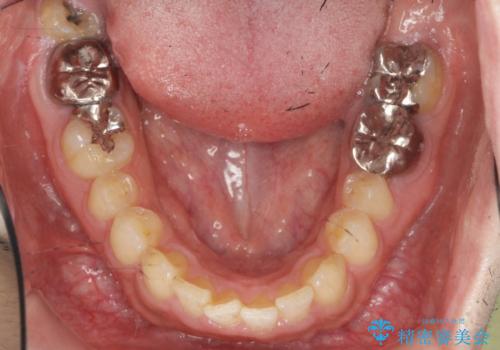

ディープバイトのマウスピース矯正

- 飛び出してしまい、隙間のある前歯をきれいに並べたい、と矯正治療を希望され来院されました。

上顎前歯を後方に引き、隙間を閉じるためには下顎前歯の絶対的な圧下を行い、深い噛み合わせを改善することが必要です。

圧下は歯の動きの中でも難しい動きの一つで時間がかかることが多いです。

前歯でチューイーをしっかり噛み、咬合圧を伝えたことで下顎前歯が圧下し、上顎前歯の隙間を閉じることができました。